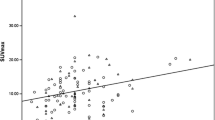

The mean SUVmax were 3.41 ± 2.07 (range 1.18–14.30), 5.17 ± 3.52 (range 1.35–19.01), 6.57 ± 3.84 (range 1.42–15.58), 7.55 ± 3.63 (range 2.30–13.60) and 6.97 ± 4.17 (range 1.15 – 16.06) for the luminal A, luminal B (HER2-negative), luminal B (HER2-positive), HER2-positive and triple-negative subgroups, respectively (Table 3 and Fig 3). SUVmax differed significantly among the five subgroups (p < 0.0001). Moreover, Bonferroni correction revealed significant differences in SUVmax between the luminal A and luminal B (HER2-negative) subgroups (p < 0.0001), the luminal A and luminal B (HER2-positive) subgroups (p < 0.0001), the luminal A and HER2-positive subgroups (p < 0.0001), the luminal A and triple-negative subgroups (p < 0.0001), the luminal B (HER2-negative) and HER2-positive subgroups (p = 0.00021), and the luminal B (HER2-negative) and triple negative subgroups (p = 0.00038).

The mean SUVmax was 3.41 ± 2.07 (range 1.18 – 14.30) for luminal A tumours and 6.08 ± 3.83 (range 1.15 – 19.01) for non-luminal A tumours (p < 0.0001). In the ROC analysis the optimal area under the ROC curve (AUC) was 0.734. A cut-off SUVmax of 3.60 yielded a sensitivity of 70.1 % (95 % confidence interval, CI, 60.5 – 79.7 %), a specificity of 66.1 % (95 % CI 59.8 – 72.3 %), and an accuracy of 67.2 % (95 % CI 62.0 – 72.5 %) for differentiation of luminal A from non-luminal A subtypes. The mean SUVmax was 7.55 ± 3.63 (range 2.30 – 13.60) for HER2-positive tumours and 5.12 ± 3.57 (range 1.15 – 19.01) for non-HER2-positive tumours (p < 0.0001). A cut-off SUVmax of 6.75 yielded a sensitivity of 65.4 % (95 % CI 47.1 – 83.7 %), a specificity of 75.2 % (95 % CI 70.1 – 80.2 %), an accuracy of 74.4 % (95 % CI 69.5 – 79.2 %), and an AUC of 0.704 for differentiation of HER2-positive from non-HER2-positive subtypes. The mean SUVmax was 6.97 ± 4.17 (range 1.15 – 16.06) for triple-negative tumours and 4.98 ± 3.42 (range 1.18 – 19.01) for non-triple-negative tumours (p < 0.0001). A cut-off SUVmax of 5.45 yielded a sensitivity of 64.1 % (95 % CI 51.2 – 72.8 %), a specificity of 67.1 % (95 % CI 61.3 – 72.8 %), an accuracy of 66.6 % (95 % CI 61.3 – 71.8 %), and an AUC of 0.649 for prediction of triple-negative tumours.